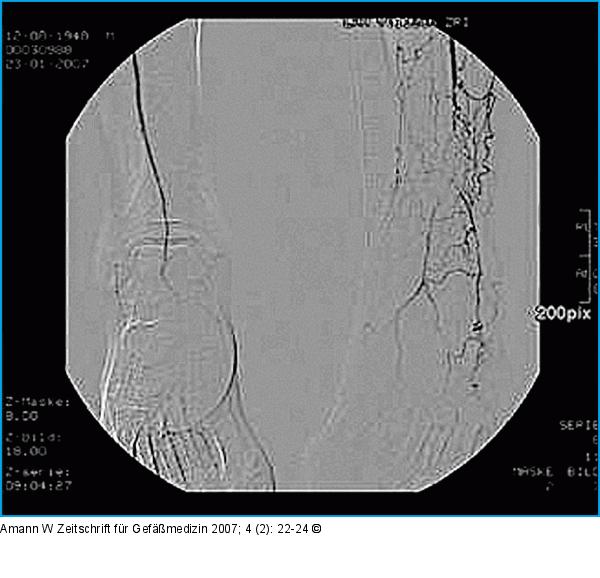

Abbildung 2: Angiographie Diagnostische Angiographie. Kurzes kaliberschwaches Empfängersegment der A. dorsalis pedis links. |

Diagnostische Angiographie. Kurzes kaliberschwaches Empfängersegment der A. dorsalis pedis links. |